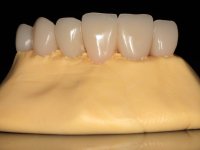

Caso 8: laboratório

O paciente foi observado conjuntamente e a dúvida que surgiu de imediato foi se seria possível com a regeneração óssea a efectuar poder ser reabilitada naturalmente a zona das papilas interdentárias. Nesse sentido foi feito um enceramento de diagnóstico que contemplaria as duas hipóteses, utilizando ou não a cerâmica gengival. A confecção desse enceramento foi fundamental para expor ao paciente a dificuldade da reabilitação. O wax-up deu origem a um mock-up que foi aprovado pelo paciente e que simultaneamente serviu de guia imagiológica. O caso foi planificado cirurgicamente e realizada uma guia cirúrgica com que foram colocados os implantes. Após 10 semanas foi feita a 1ª impressão para confecção da ponte provisória. Foram criados os primeiros perfis de emergência na gengiva artificial e foi digitalizado o modelo. Por processo de CAD-CAM foi confeccionada uma ponte provisória aparafusada baseada no enceramento de diagnóstico. A ponte trabalhou durante 8 semanas os tecidos moles que foram fielmente copiados numa impressão com técnica de moldeira aberta. Os transferes foram individualizados com resina composta para copiarem fielmente os perfis de emergência criados pela ponte provisória. Confeccionado o modelo de trabalho definitivo, foi realizada uma infra-estrutura em zircónio seguindo a orientação do enceramento de diagnóstico. O assentamento da infra-estrutura foi testado em boca e simultaneamente foi novamente impressionados os tecidos moles com um silicone fluido. Nessa consulta foi feito o levantamento da cor. Os dentes 13 e 23 apresentavam uma saturação anormalmente forte que resolvemos não valorizar, optando por privilegiar a relação com o sector antero-inferior. Foi realizada uma nova gengiva artificial com a impressão que acompanhou a impressão de arrasto com a infra-estrutura. Após a colocação da cerâmica na infra-estrutura foram coladas as meso-estruturas. O trabalho final foi aparafusado lentamente permitindo a adaptação dos tecidos moles.